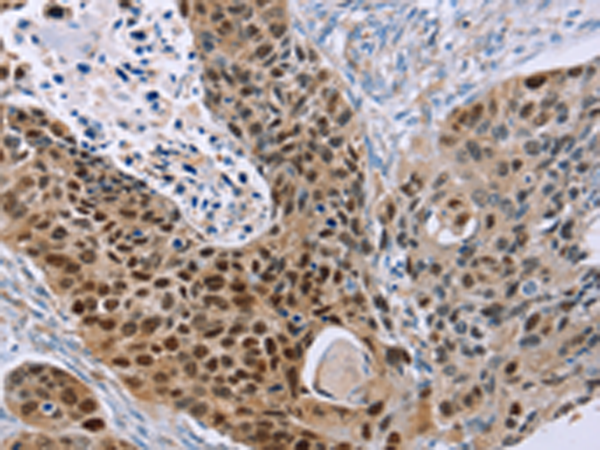

分类: 科研抗体货号: P08528别名: p8; C6.1B; MTCP1; MTCP1B; MTCP1NB; p8MTCP1应用: IHC反应种属: Human, Mouse